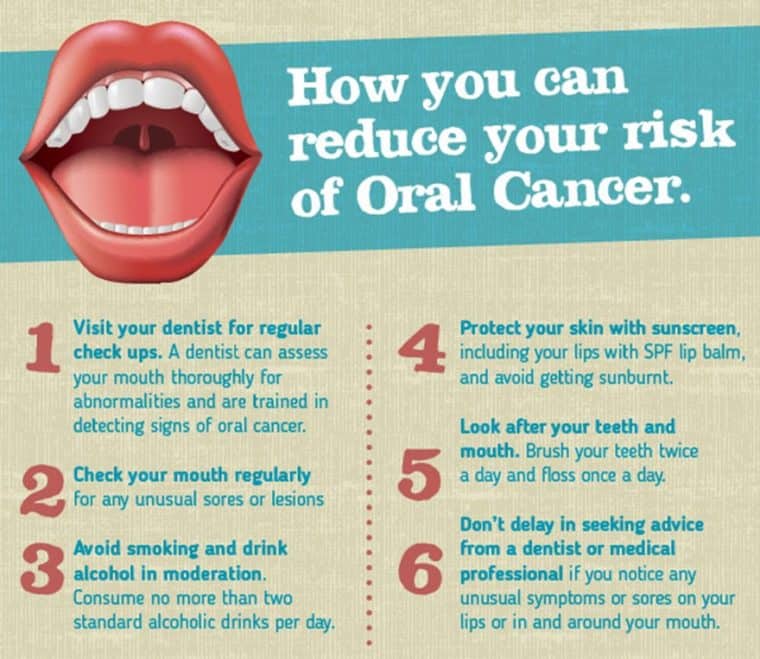

Warning Signs Of Oral Cancer Symptoms And Risk Factors

Oral Cancer Awareness Early Detection Is Key Oral And

A Dentist Shares How To Prevent Oral Cancer Signs And Symptoms

Oral Cancer Screening At Freedom Dental Melbourne

Oral Cancer Its Causes Symptoms Diagnosis And Prevention

How To Spot Mouth Cancer Oral Health Foundation

Oral Cancer Symptoms 13 Signs You Might Ignore The Healthy

Warning Signs Of Oral Cancer Symptoms And Risk Factors